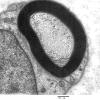

PERIPHERAL NEUROPATHY

2 NORMAL AXON (2)